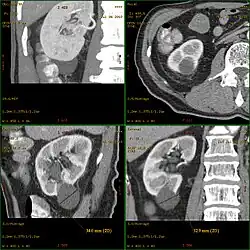

Kyste rénal

Un kyste rénal est une sorte de poche sur le rein contenant du liquide. Sa formation est assez fréquente en vieillissant. Les kystes sont souvent bénins (kyste simple) et ne nécessitent aucun traitement ou suivi particulier.